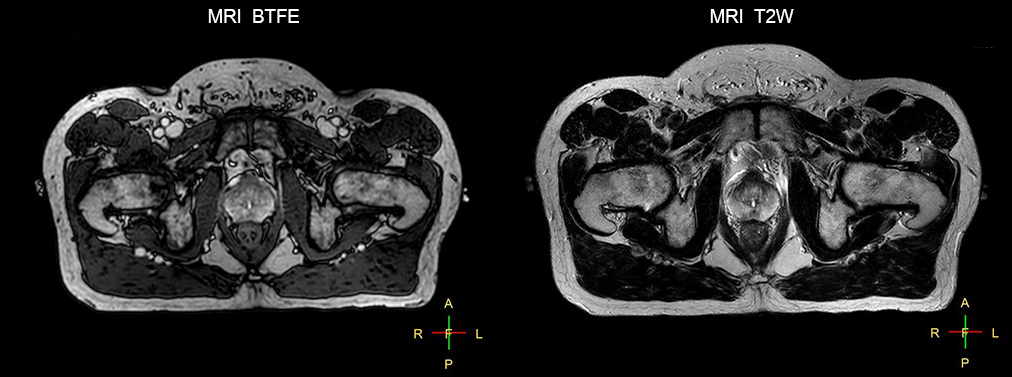

“We currently use MR-RT mainly in the abdomen and pelvis region: prostate, colorectal, pancreatic, cervical, and liver. Also in the brain, we are starting to use it,” says Dr. Yan.

Impressive clinical benefits for prostate

“The biggest problem for CT-based planning, especially in prostate, is you can’t see the cancer very well,” says Dr. Stevens. “On CT it can be quite challenging to see the edge of the prostate especially at the apex. When the edge of the prostate can’t be delineated well on CT, radiation oncologists will increase their margins a little bit so they don’t miss it, but that can also increase toxicity.”

“Using MR, the prostate is well delineated. We quickly see the edges of cancerous tumors like in prostate cancer, and as normal structures can be defined, we can optimize the treatment plan to protect these organs and their normal function. This can potentially improve the outcome. And it improves workflow as well. We can contour more quickly, confident that the tumor is going to be in the field.”

“The Ingenia 3.0T MR scanner provides high resolution allowing us to make scans fast for the patients. It also gives the potential to include methods like MR spectroscopy and diffusion weighted Imaging, which we’re in the process of doing right now,” Dr. Stevens adds.